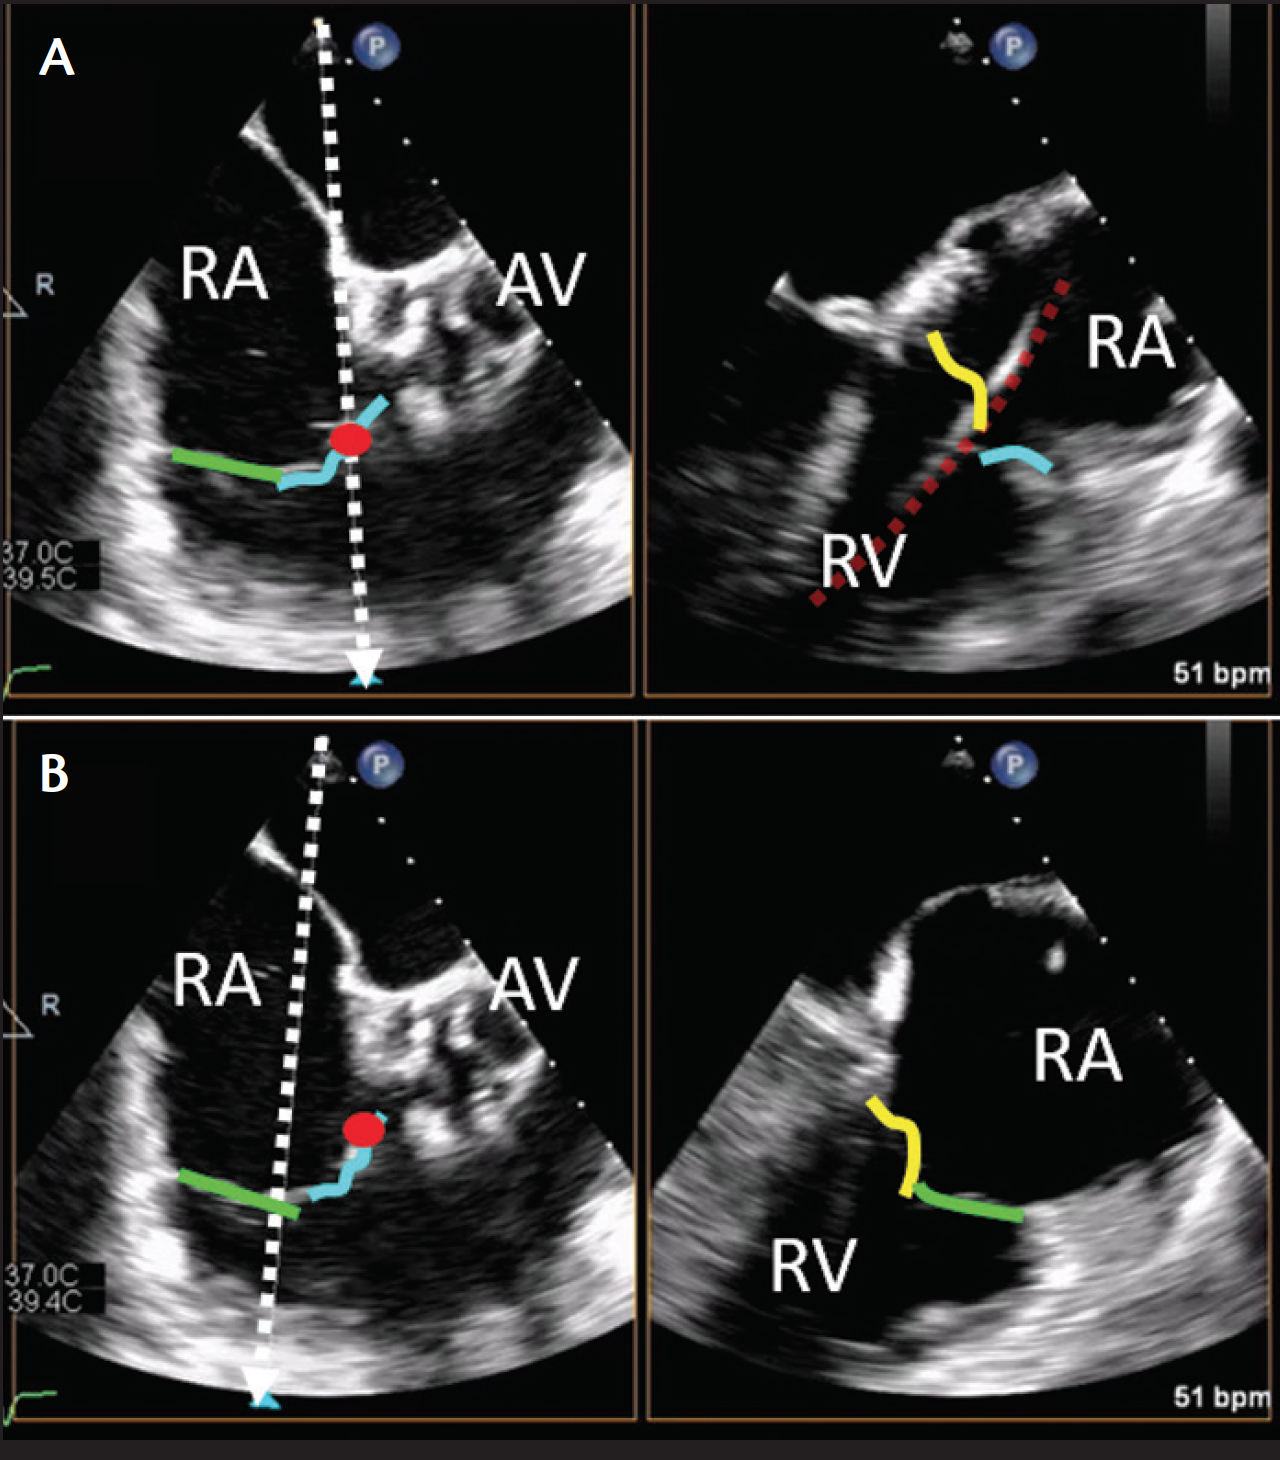

Figure 2. Mid-esophageal four-chamber view of the tricuspid valve. In this example, a temporary pacing wire (red circle or dashed line) has been placed in the septal-anterior commissure to help identify the anatomy. The mid-esophageal four-chamber view, obtained by clockwise rotation of the probe to center the tricuspid valve, will typically image the septal and anterior leaflet (A); however, with retroflexion of the probe, the septal-posterior coaptation is imaged (B). Abbreviations: LA, left atrium; LV, left ventricle; RA, right atrium; RV, right ventricle.

First, the commissure between the anterior and septal leaflets is adjacent to the noncoronary cusp of the aortic valve; the right coronary cusp is adjacent to only the anterior leaflet. Second, although a small (anterior) portion of the septal leaflet may be seen if the aortic valve is in view, most of the septal leaflet is attached to the interventricular septum. Third, the coronary sinus enters the right atrium at the commissure between the septal and posterior leaflets. Finally, the right atrial appendage is directly superior to the anterior leaflet. Any two-chamber imaging plane of the RV will tend to image the anterior and posterior leaflets as long as the anterior (curved, right atrial appendage in view) and posterior (flat, on the diaphragm) walls of the RV are imaged.80

A comprehensive TEE examination of the TV should include imaging from several depths and multiplane angles. Multilevel imaging begins at the midesophageal depth. The four-chamber view permits visualization of the septal and anterior leaflets, particularly if the probe is slightly anteflexed (Figure 2A). If retroflexed (Figure 2B), the septal-posterior leaflet coaptation is imaged.